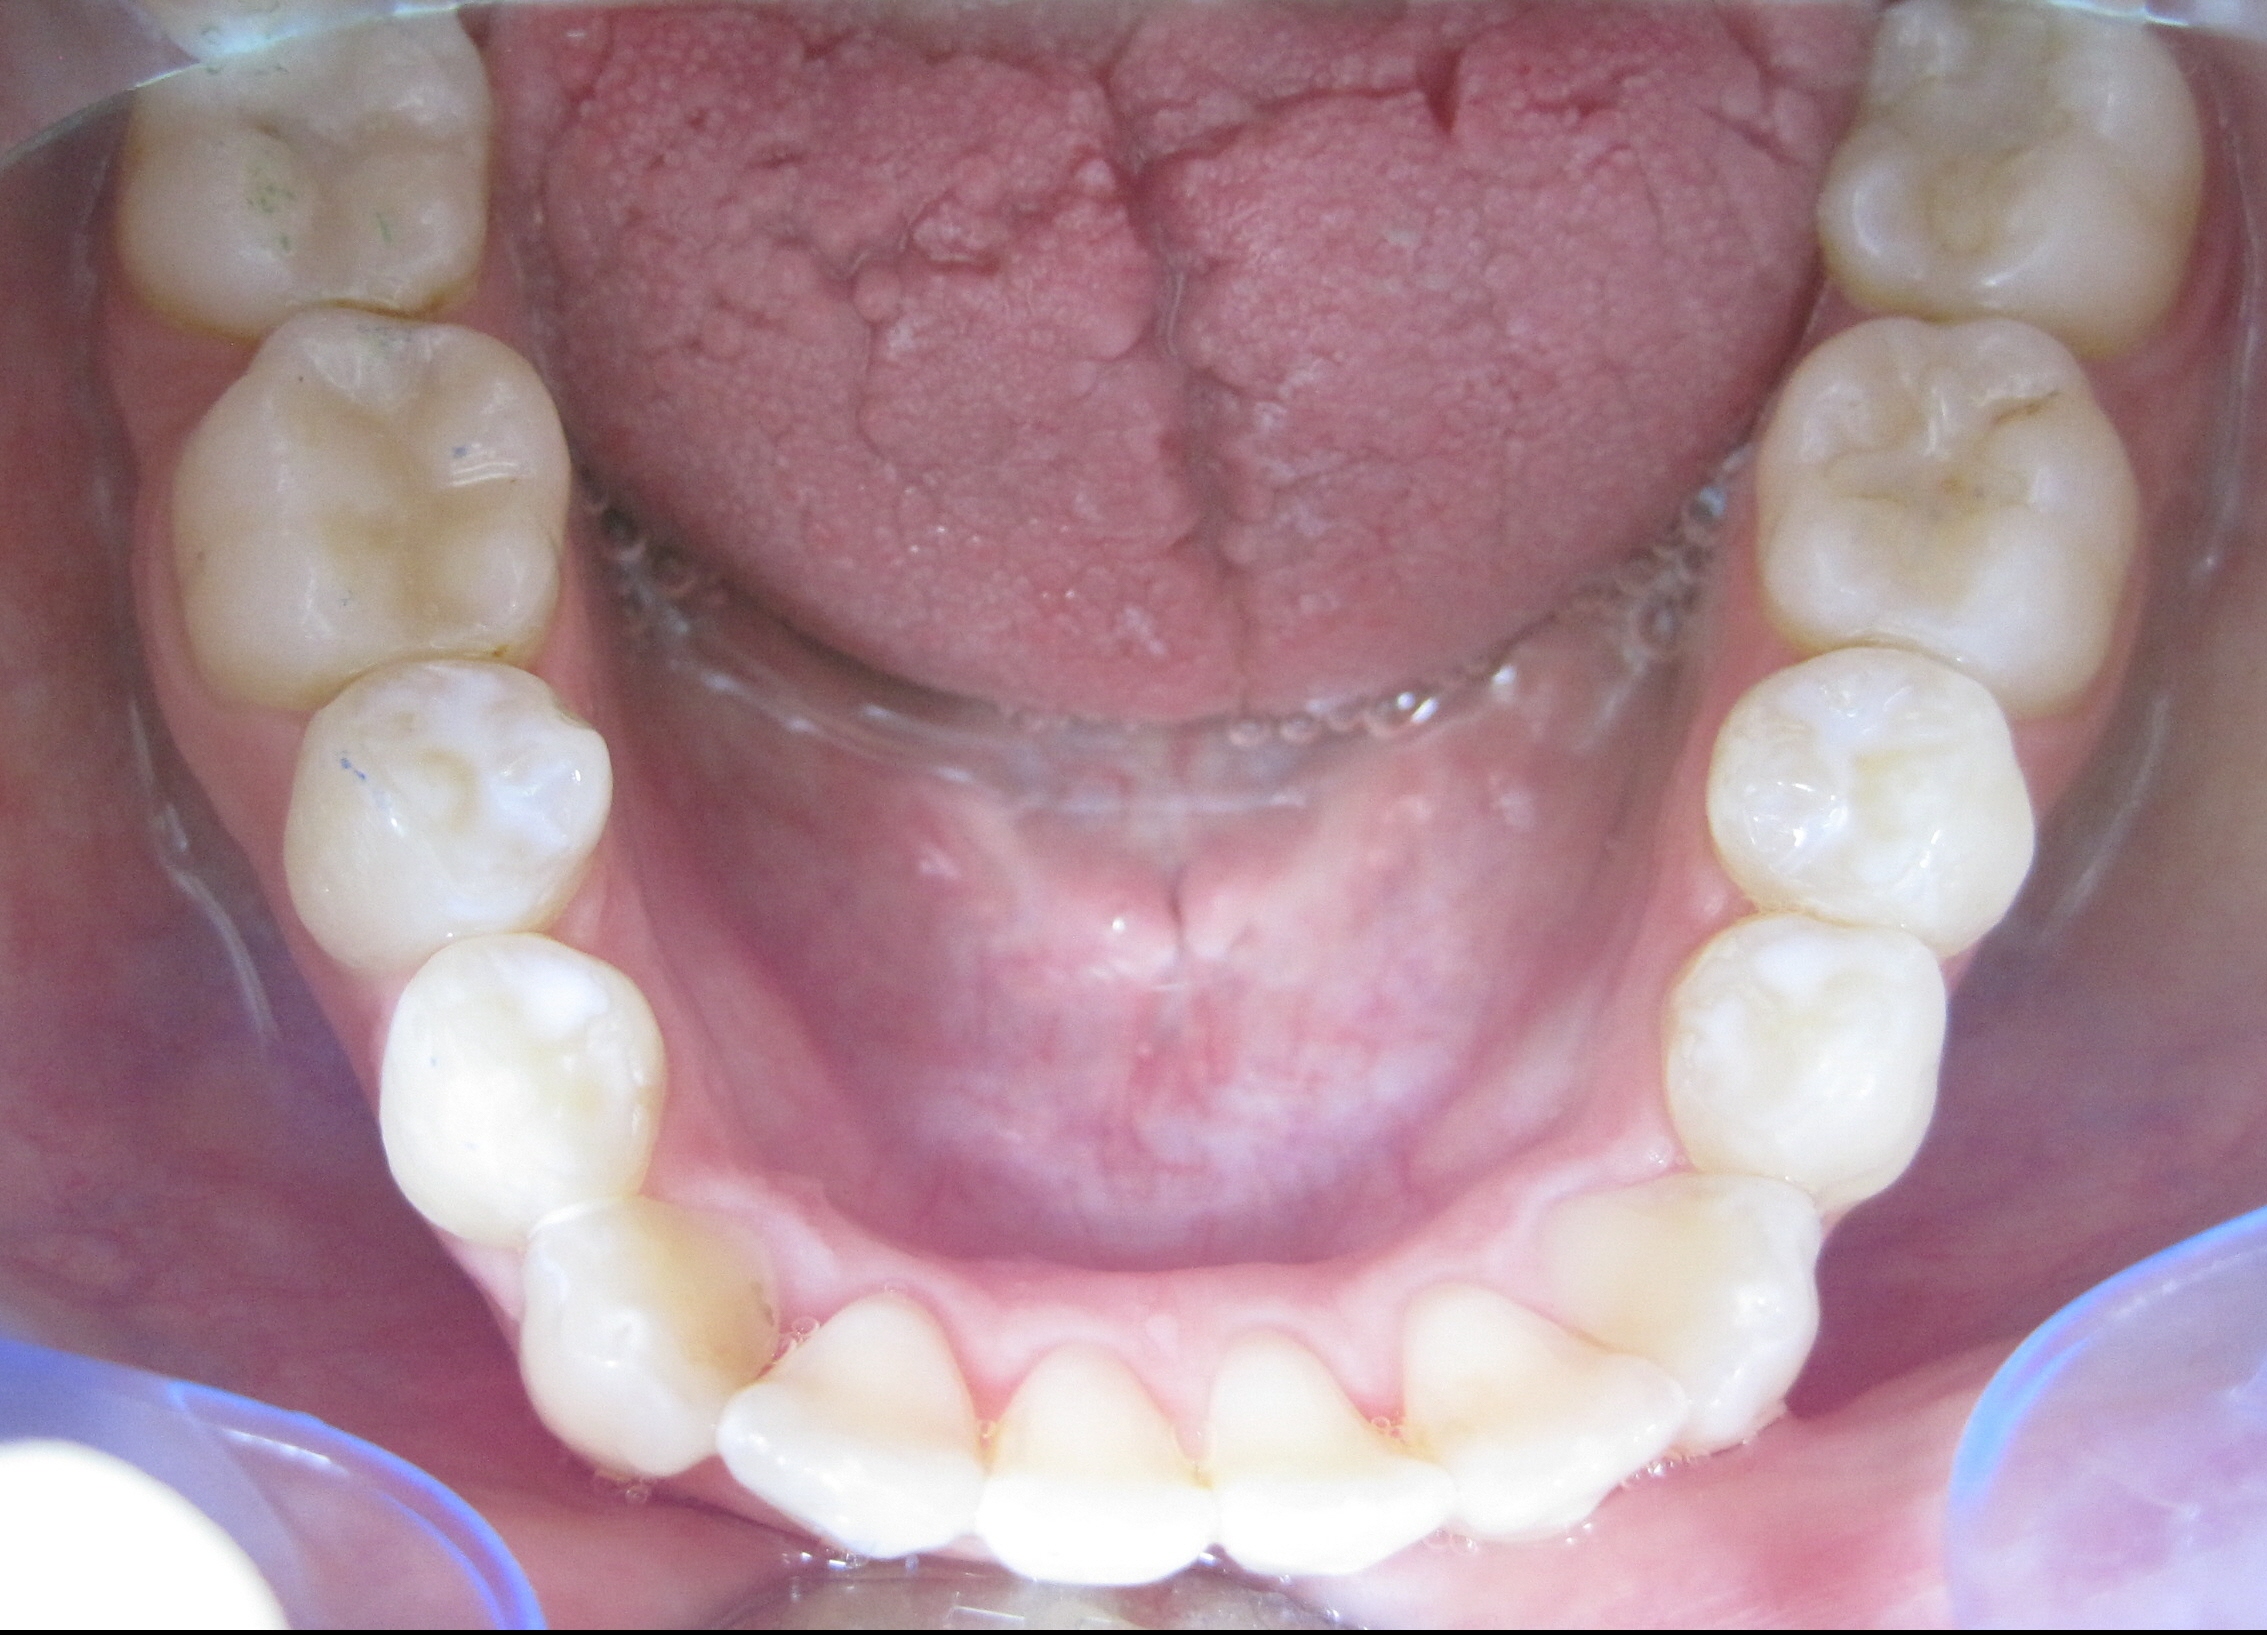

Patient 41 Jahre, massiver Unterkiefer-Frontzahn-Engstand: Alphalignbehandlung mit 15 Alphalignern, d.h. 7,5 Monate Behandlungszeit, jetzt viel bessere Pflege möglich, da akkurater Zahnbogen, dadurch geringeres Risiko von Karies sowie Zahnfleisch- und Zahnbetterkrankungen

nachher (nach 7,5 Monaten Behandlungszeit)